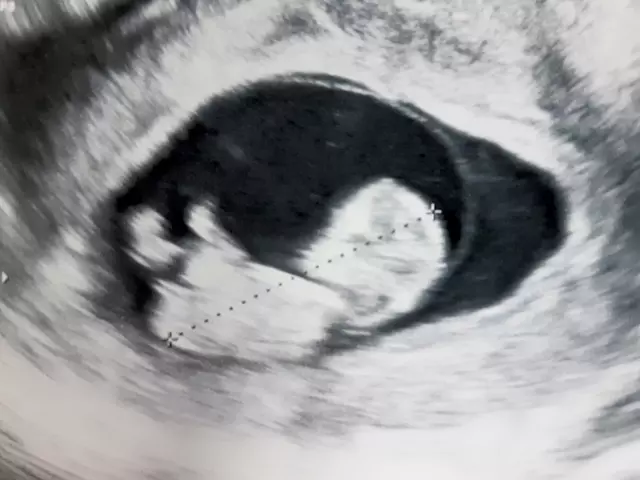

胎囊(たいのう)とは、妊娠のごく初期に超音波検査で確認できる、子宮内の「黒い丸」のように映る袋のことです。妊娠4週〜5週ごろに確認でき、赤ちゃんが育つためのベースとなる重要な構造です。袋の中は羊水で満たされており、胎芽(後に胎児となる組織)や胎盤など、成長に必要な組織がここから発達していきます。

この胎囊の確認は、妊娠が成立したことを示す最初の確かなサインといえます。

- 妊娠4週後半〜5週前半

超音波検査で、子宮内に小さな黒い円(胎囊)が見えるようになります。 - 妊娠5週後半〜6週前半

胎囊の中に「胎芽(たいが)」と呼ばれる胎児の原型が映り始めます。 - 妊娠6週以降

超音波で胎芽の心拍が確認でき、妊娠が順調に進んでいるかどうかの重要な指標となります。